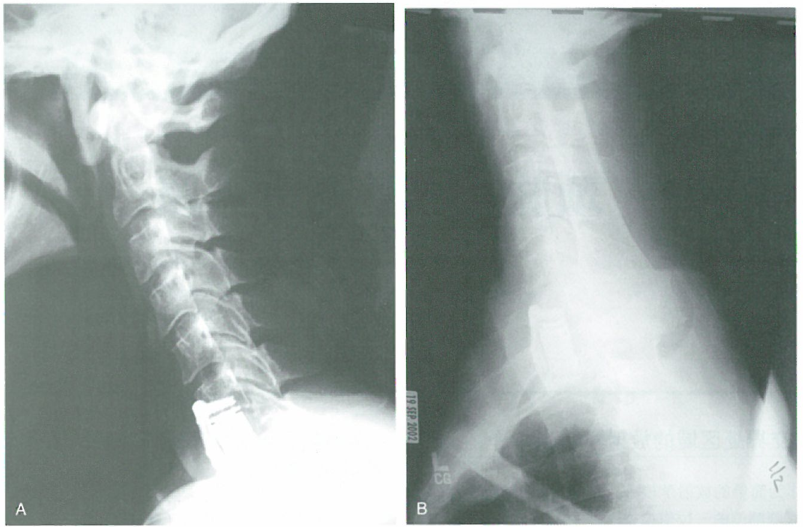

一项研究表明,作为简单的放射学检查,在颈椎需进行包括前后位和双侧侧位的三位像检查。海外医疗机构爱诺美康了解到,在颈胸交界处,肩关节可能阻碍对病灶的正确显示(图,A)。从技术角度来说,对该区域进行充分的显影可能较为困难,在至少30%的患者,无法通过三位像显示C7-T1区域。而进行双斜位和游泳者位检查可以起到帮助作用。在标准前后位和侧位检查未能显示颈胸交界处的患者,进行游泳者位和仰卧斜位检查可以显示椎体的外形(图,B)。但是仰卧斜位像更安全,患者所受放射剂量较小,通常能更好地显示颈胸交界处的后侧附件结构。

海外医疗机构爱诺美康介绍,当在C7和T1节段进行椎体切除时,不能简单地通过侧位像评估植人物的位置(图,A)。通过斜位像可以相对容易地辨别外形(图,B)。如对C7-T1区域进行充分的评估,就需要进行比X线平片优越的CT检查。CT可以正确显示横突和肋骨头周围的解剖结构,还可以提供矢状位图像,以便于术者决定植入物和器械的正确位置。如果进行CT检查,通过轴位和矢状位检查可以轻易显示植骨和内固定器械的位置(图,C和D)。